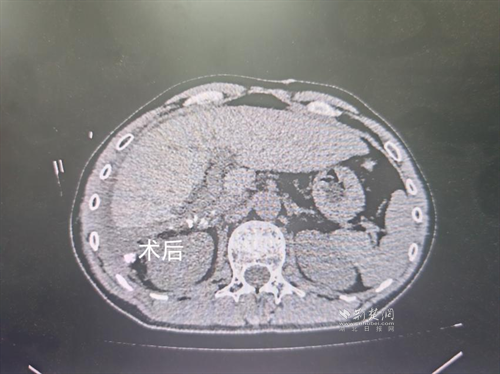

經(jīng)過肝膽外科牽頭組織的多學(xué)科MDT會診,團隊確認(rèn)其適合接受當(dāng)前國際先進的釔90樹脂微球選擇性內(nèi)放射治療。治療僅一個月后,患者病灶即從10cm縮小至6cm;術(shù)后六個月復(fù)查顯示,病灶體積進一步縮小近40%,影像學(xué)檢查提示完全緩解,臨床分期成功轉(zhuǎn)化,達到手術(shù)切除標(biāo)準(zhǔn)。